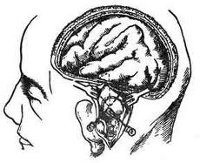

Пункция абсцесса мозга. Диагностическая операция, при которой жидкость извлекается из полости абсцесса для дальнейшего исследования. Операция назначена для уточнения диагноза, изучения содержимого абсцесса, определения типа микроорганизмов, вызвавших инфекцию. Кроме того, методика используется для введения контрастного вещества и последующего изучения патологического образования с целью выяснения его границ. Результаты пункции абсцесса головного мозга необходимы для точной диагностики заболевания и выбора эффективной тактики лечения.

Если есть подозрение на абсцесс мозга, невролог может выполнить пункцию для уточнения диагноза, дифференцирования абсцесса от разлагающейся опухоли, гематомы, демиелинизации, гранулемы или кисты. В клинической неврологии пункция абсцесса также проводится для введения контрастного вещества и последующего магнитного резонанса, что позволяет точно определить местоположение патологического очага, его границы, наличие капсулы или ее разрыв с проникновение гноя в окружающие ткани. Эти данные имеют большое значение для выбора тактики лечения и планирования операции. Изучение содержимого абсцесса, полученного после пункции, позволяет выявить патогенные микроорганизмы, которые вызвали гнойные состояния, и назначить лечение на основе их чувствительности к антибиотикам. Если диагноз подтверждается в процессе манипуляции, можно выполнить одноэтапное измерение: удаление гноя и введение препарата в полость абсцесса.